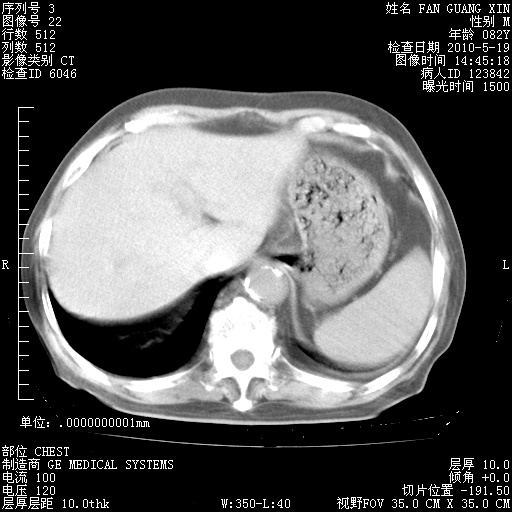

治疗3周后的肺部CT纵隔窗

从胸部影像学来看,的确有好转。至于目前为何发热不甚清楚?除了发热还有其他症状如有无喀痰,痰呈丝状吗?等等。尽量搜寻有无致发热其它可能原因?真菌?其它?如果的确无其他致发热的原因,考虑将甲强龙调至60-80mg bid/日。免疫全套基本无异常,考虑多系特发性肺间质纤维化